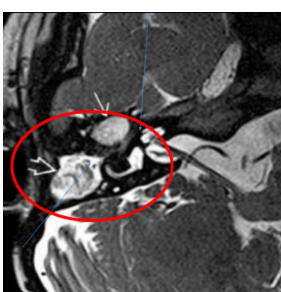

Q

De que enfermedad se trata y qué complicacion está presentando

A

Mastoiditis con invasión a SNC con un absceso que provoca una meningitis

Complicaciones de la mastoiditis

Abscesos que pueden extenderse a fosa posterior y fosa craneal media